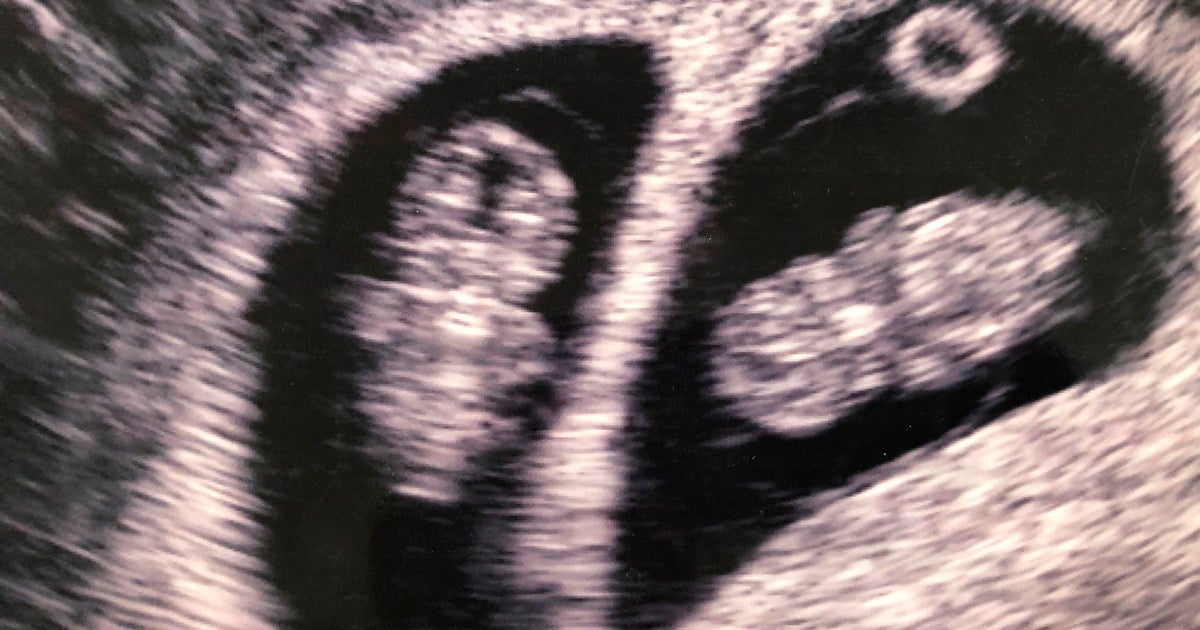

A 32-year-old woman from Alabama who was born with two uteruses and became pregnant in both gave birth to twin girls on different days, she announced on social media Friday.

A 32-year-old woman from Alabama who was born with two uteruses and became pregnant in both gave birth to twin girls on different days, she announced on Friday.